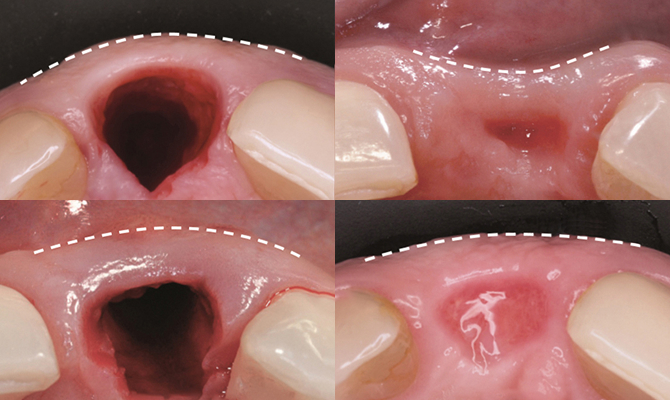

잇몸뼈 손실을 최대한 줄여주는 급속 골이식(i-GBR)

치아를 발치하는 순간 부터 잇몸뼈는 빠른 속도로 흡수됩니다.

발치 후 잇몸뼈는 자연적인 흡수가 일어나게 되는데, 이런 변화의 대부분은 발치 후 3개월 내에 발생하게 되며, 발치 1년 경과 시 원래 잇몸뼈 폭의 절반이 흡수됩니다.

급속골이식(i-GBR)은 심한 잇몸뼈 소실로 임플란트를 심기 어려운 경우에 골이식재와 특수 차폐막을 이식하여 임플란트를 심기에 좋은 뼈를 만들면서, 동식에 각화치은도 매우 두껍게 생성하는 술식입니다.